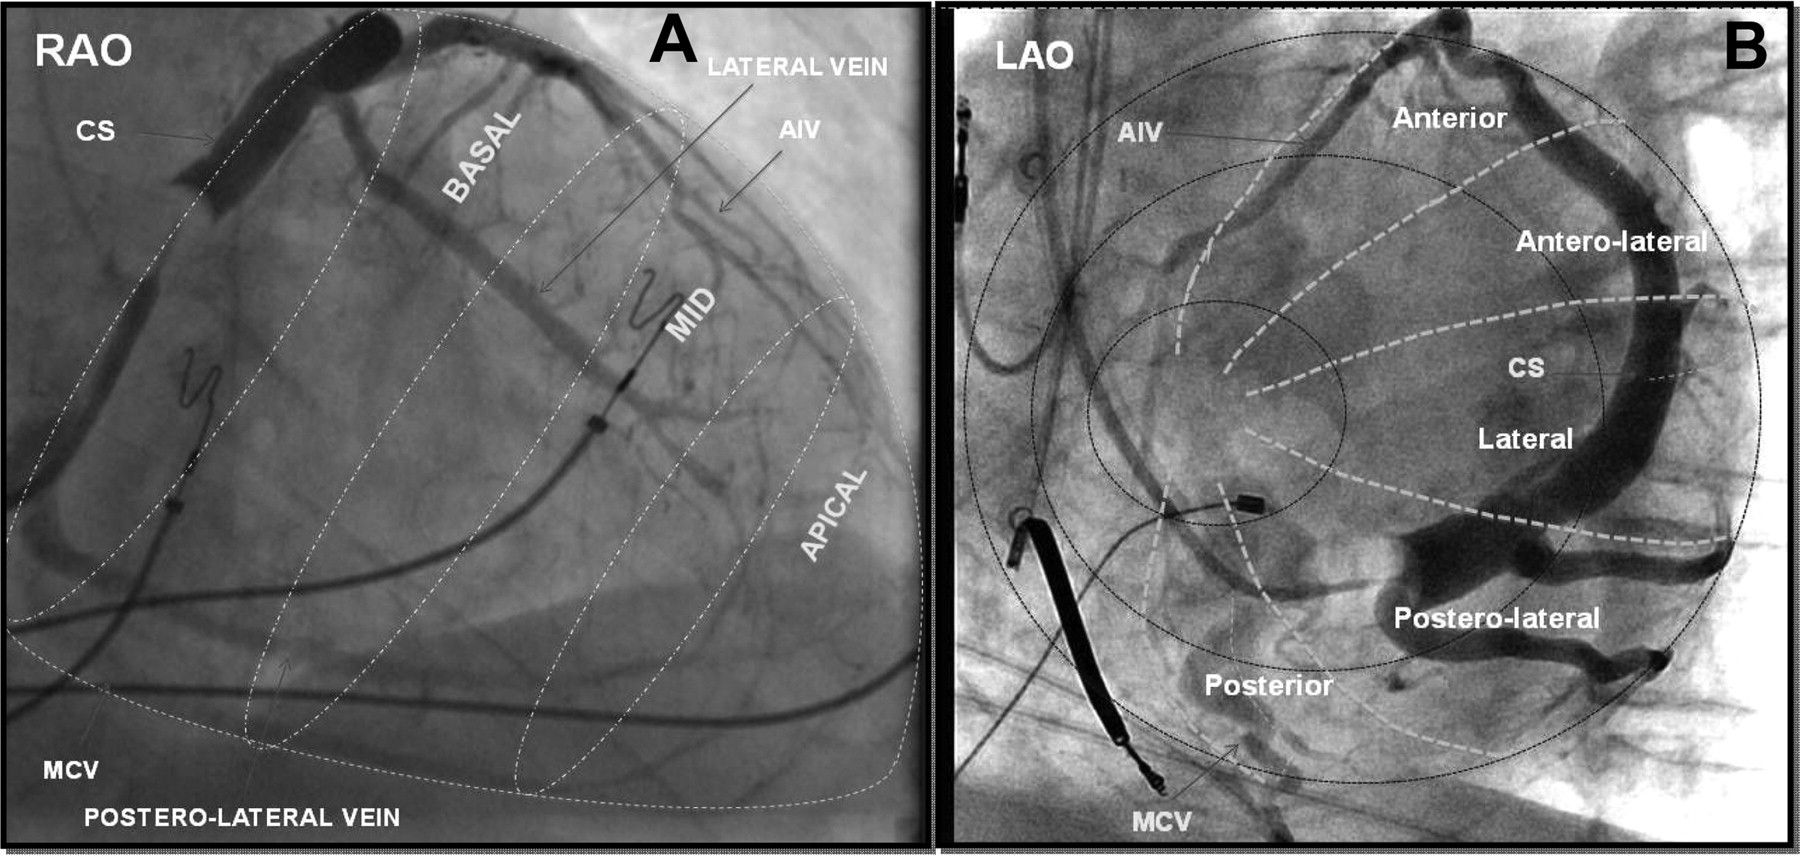

Singh JP, Klein HU, Huang DT, Reek S, Kuniss M, Quesada A, Barsheshet A, Cannom D, Goldenberg I, McNitt S, Daubert JP, Zareba W, Moss AJ. Left ventricular lead position and clinical outcome in the multicenter automatic defibrillator implantation trial-cardiac resynchronization therapy (MADIT-CRT) trial. Circulation. 2011 Mar 22;123(11):1159-66.